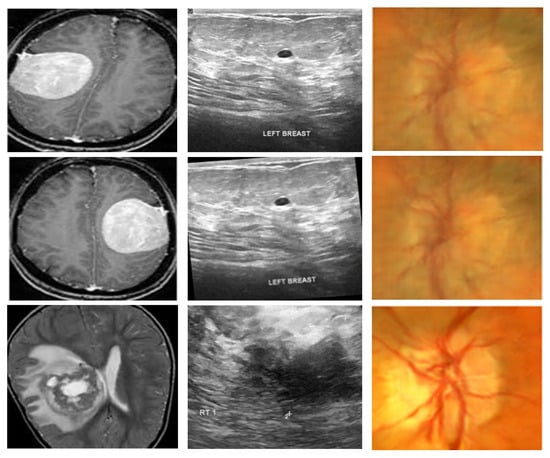

To assess the generalizability and effectiveness of the proposed framework, experiments are conducted on three publicly available medical imaging databases that span various modalities and diagnostic complexities. The summary of the datasets is given in Table 4 whereas the representative samples from these datasets are given in Figure 2.

The first dataset, BTTypes [38] is sourced from the open dataset Brain MRI Images for Brain Tumor Detection [39], which initially comprised 11 benign and 12 malignant MRI scans. For enhanced sample diversity and stronger training robustness, the BTTypes authors employed multiple augmentation strategies, resulting in a total of 2400 MRI images, which were balanced equally between 1200 benign and 1200 malignant cases.

4.1.2. Ultrasound Breast Cancer Images (Dataset 2)

The second dataset, Breast Ultrasound Images for Breast Cancer [40], is used for the detection of breast cancer using ultrasound images. Rotation and sharpening augmentation techniques were employed to expand the dataset to 9016 images, comprising 4574 benign and 4442 malignant images.

4.1.3. ACRIMA Retinal Fundus Images (Dataset 3)

The third dataset is ACRIMA, one of the subsets of the Generated Eye Dataset for Glaucoma Detection on Kaggle [41]. The entire repository combines five collections (RIM-ONE, ACRIMA, HRF, Drishti-GS, and ORIGA-LIGHT), comprised of a total of 30,000 images. For our research, only the ACRIMA subset was employed, consisting of 6000 retinal fundus images, divided into 3000 glaucoma cases and 3000 normal cases.

This cross-dataset assessment guarantees that the designed framework is tested on various imaging modalities (MRI, ultrasound, and retinal fundus) and disease categories (brain tumor, breast cancer, and glaucoma) to ensure robustness and flexibility.